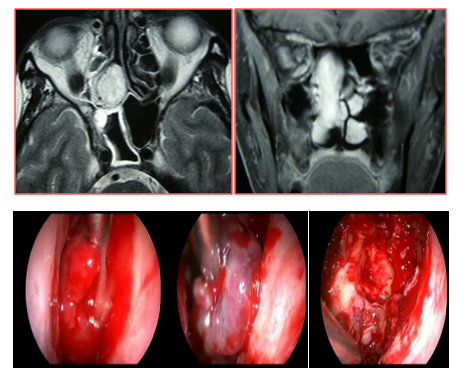

It was not necessary to perform an external approach, nor did they receive blood transfusions during or after the surgery. The patient with the tumor located in the posterior ethmoid was operated by the endonasal approach and the vascular pedicle was controlled prior to the resection of the tumor by cauterizing the sphenopalatine artery (Figure 3).

The intraoperative histological study was reported as a vascular tumor without atypia and the deferred histopatological study as a cavernous hemangioma. The nasal cavity hemangioma was resected by endonasal approach. The intraoperative excisional biopsy was reported as a cavernous hemangioma (Figure 4). Two had a nasal tamponade that was removed at 48 hours and in 2 a hemostatic matrix was used (surgifló). The length of stay was 24 hours in three and 48 hours in another. There were no complications. The follow-up was greater than 5 years in two, 2 years in one and 1 year in another patient. No recurrences were detected.